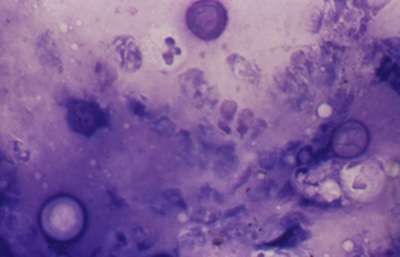

Coloración de Giemsa

En un frasco de Copli colocar 10 ml de la solución del colorante de Giemsa con 90 ml de un buffer fosfato 1/15 M y pH 6.8. Colorear el extendido fijado por 20 minutos. Lavar en agua corriente y dejar secar al aire. Aclarar en xileno por 5 minutos y montar con un medio de resina.

Los quistes Acanthamoebas midien de 10 a 16 µm de diametro, con capsula de forma circular o poligonal, a veces con angulaciones y ondulaciones, (Figura 41) teñido densamente azul oscuro. Membrana plasmática con tinción más tenue, concéntica, o retraida o colapsada asimétricamente. Coloración variable del citoplasma. (Figura 42, 43, 44 y 45)

Fig. 41 Giemsa. Original x400

Fig. 42 Giemsa. Original x200

Fig. 43 Giemsa. Original x160

Fig. 44 Giemsa. Original x160

Fig. 45 Giemsa. Original x200

Fig. 46 Giemsa. Original x160

En ocasiones cariosoma central prominente (en ojo de buey) (Figura 46) y quistes claros, vacios, compuestos sólo por la doble pared del quiste y membrana plasmática.

Cuando los quistes se localizan en el epitelio o en detritus colágenos y fibrinoides, el ectoquiste puede ser refringente, transparente o tenuemente azulado y el tendoquiste densamente coloreado de azul por el Giemsa. (Figura 47)

Los trofozoitos son más difíciles de visualizar, siendo mayores que los quistes. En preparaciones fijadas, son de forma circular, con pequeño núcleo y citoplasma con numerosos organelos y vacuolas (Figura 48)